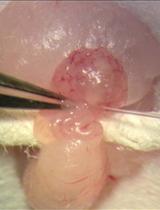

Procedure